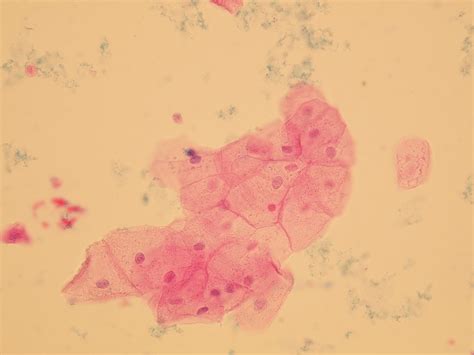

Squamous epithelial cells are a type of epithelial cell characterized by their flat, scale-like shape. These cells play a crucial role in various tissues and organs throughout the body, providing a protective barrier and facilitating essential functions. One specific type of squamous epithelial cell, known as Squamous Epithelial Cells 610, has garnered significant attention in the fields of histology and pathology. This article delves into the characteristics, functions, and clinical significance of Squamous Epithelial Cells 610, offering a comprehensive understanding of their role in human physiology and disease.

Squamous Epithelial Cells 610 are a specific subtype of squamous epithelial cells that exhibit unique characteristics. These cells are typically found in the stratified squamous epithelium, which is composed of multiple layers of cells. The number “610” in their designation refers to their specific morphological and functional properties, which distinguish them from other types of squamous epithelial cells.

• Flat and Scale-Like Shape: These cells have a flat, scale-like appearance, which allows them to form a tight, protective barrier.

• Stratified Structure: Squamous Epithelial Cells 610 are arranged in multiple layers, providing enhanced protection and durability.